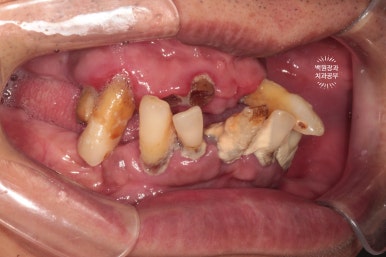

측면에서 본 사진에서도 더 이상의 희망이 없어보입니다.